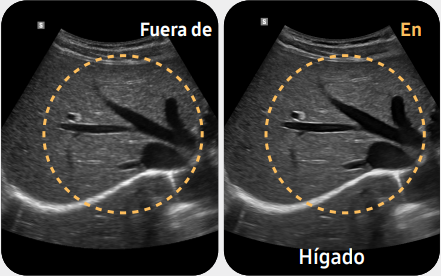

Funciones avanzadas abdominales, como EzHRI™, TAI™ y TSI™, para cuantificar el hígado graso.